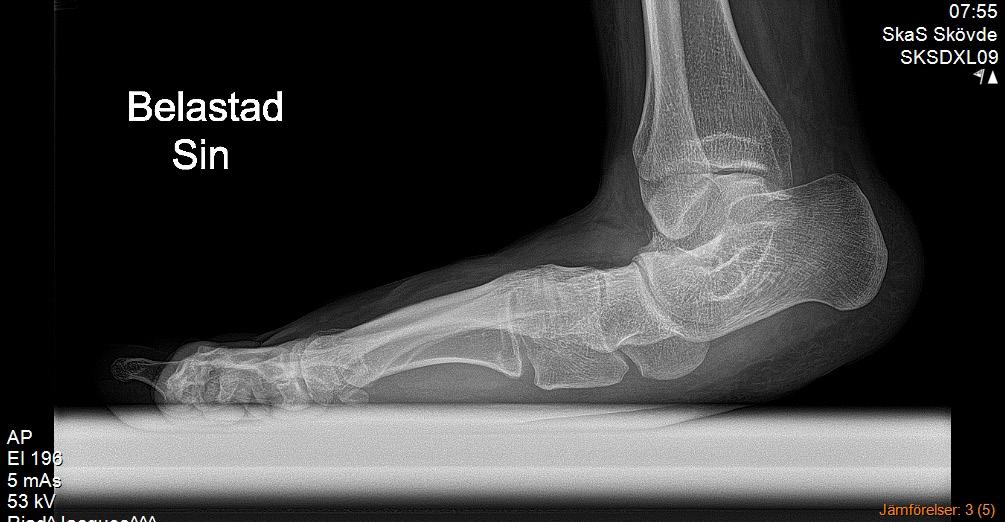

Sannolikt normalt/fysiologiskt hos barn om den är bilateral. Plattfothet undersöks bäst bakifrån när barnet står på hela foten och sedan ställer sig på tå. Då ser man hur bakfoten går från valgus vid belastning till varus vid tåstående. Likaså kan man se att det utvecklas ett längsgående medialt fot valv när barnet ställer sig på tå jämfört med när hela foten belastas. Se bild 1.

Sannolikt. Plattfotheten beror nog mest på flexibla fötter som inte har något strukturellt fel. Observera att det normala är bilateral plattfothet. Unilat eral betyder att en fot är platt, pes plano valgus, eller att den andra är i varus, ibland cavo varus, vilket inte är normalt. Om det finns en tydlig asym metri och fotfelställningen är förvärvad behöver man tänka på möjlig neuropati eller pro cess i spinalkanalen. Se bild 2.

Plattfothet är en felställning i första hand och inte en diag nos. En individuell bedömning av var felställningen sitter och vad den kan bero på behövs. Se bild 3.